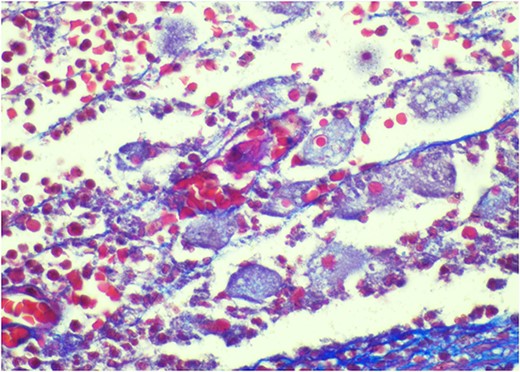

Pathology resulted on post-operative day three showing an inflamed appendix, 1.4 cm in diameter, with an exudative-filled lumen. On microscopic stains, there was evidence of acute appendicitis with frequent scattered unicellular organisms within areas of ulcerated appendiceal mucosa and submucosa (Figs 6 and 7). These cellular forms have round cell membranes, single prominent round eosinophilic nuclei and foamy cytoplasm (Fig. 5). Occasional forms show evidence of erythrophagocytosis (Fig. 3). Forms were also highlighted by trichrome and PAS special stains (block A1) and were negative for CD68 (a marker of macrophages; block A1) (Figs 2–4). These morphologic features are most consistent with E. histolytica, which is a pathogenic parasite in the lower GI tract, and likely the causative agent for acute appendicitis in this case.

Trichrome stain—parasites are positive; erythrophagocytosis supporting Entamoeba histolytica.